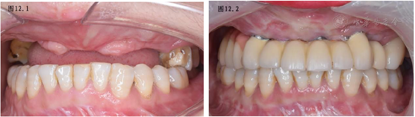

种植体骨结合良好,无炎症。佩戴临时可摘义齿3个月,无颞颌关节功能不适,完成上颌种植体水平取模(图10),马龙桥修复缺失牙(图13),26、27全瓷冠修复,按临时义齿咬合关系完成最终咬合重建(图12)。

专科检查:双侧颧骨、下颌角过大,面中部凹陷。上唇唇正中可见术后瘢痕,红唇菲薄、唇珠消失(图1)。恒牙列,16-25缺失,17近中牙根外露,I°松动,26牙近中牙冠缺损。患者缺牙区牙槽突不平整,前庭沟变浅,水平向、垂直向咬合关系丧失(图2)。